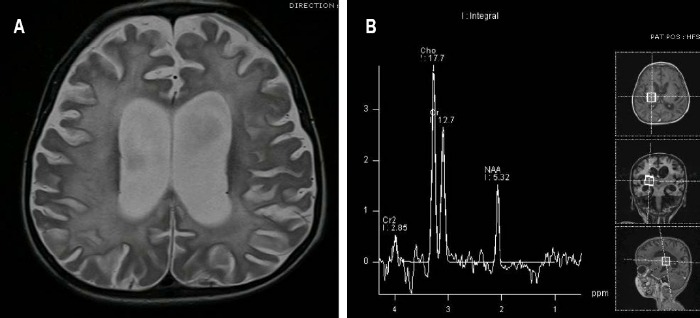

(A) T2-взвешенная аксиальная томограмма: симметричные области гиперинтенсивнности в белом веществе, которые распространяются на подкорковую область. Явления атрофии с выраженными бороздами и расширением желудочков.

(B) МР-спектроскопия: Снижение пика N-ацетиласпартата (NAA), несколько повышен пик холина (Cho).

- пораженные области демонстрируют повышение МР сигнала на T2ВИ/FLAIR изображениях;

- нередко наблюдается также их контрастное усиление в T1ВИ после внутривенного контрастирования;

- атрофия головного мозга проявляет себя выраженностью борозд, истончением извилин и равномерным компенсаторным расширением желудочков;

- при проведении МР-спектроскопии может обнаруживаться:

— отсутствие или снижение пика N-ацетиласпартата;

— повышение пика холина и мио-инозитола;

— повышение пика лактата;

Излюбленная локализация изменений: перивентрикулярное и субкортикальное белое вещество; базальные ядра, мозолистое тело, таламусы и спинной мозг поражаются реже. С прогрессированием процесса появляются признаки атрофии полушарий, мозжечка и продолговатого мозга, вплоть до тотальной потери белого вещества на терминальной стадии. Серое вещество вовлекается в сравнительно меньшей мере.